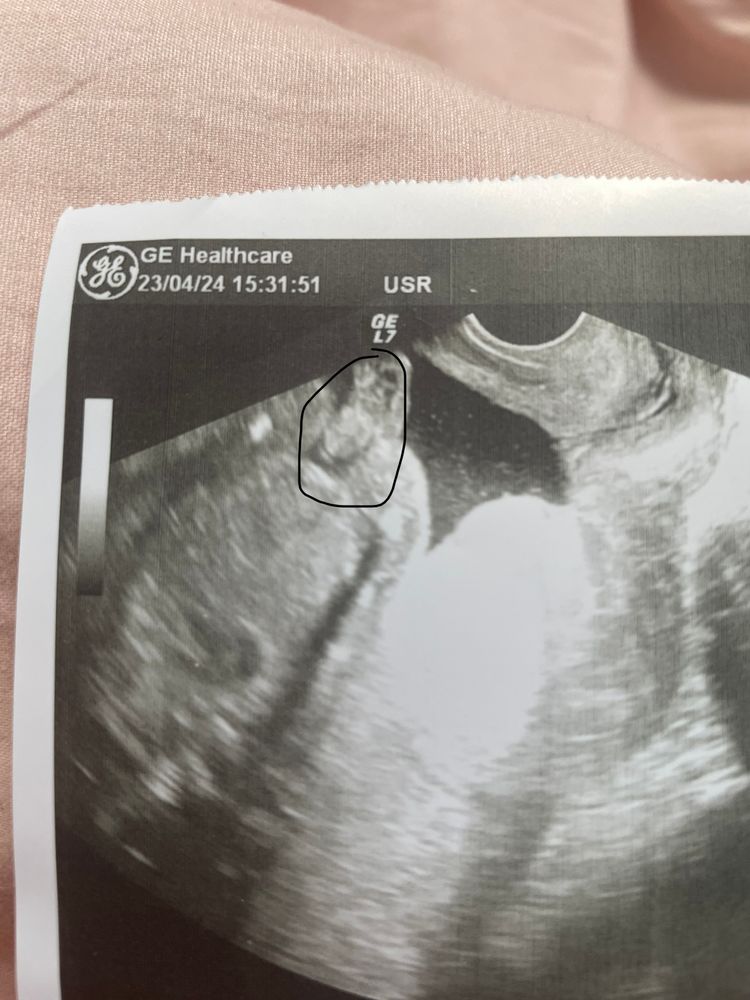

УЗИ 17,5 недель

Мальчик. У девочки на этом сроке ничего не торчит.

Ну да, спорное фото, может и кусочек от пуповинки быть

Не очень удачный снимок,вообще не понятно что где

Катя, отметила на фото

Евгения , мальчик 😀у девочки по другому ,там 2 полосочки и видно сразу

Кто будет? Пол ребенка.